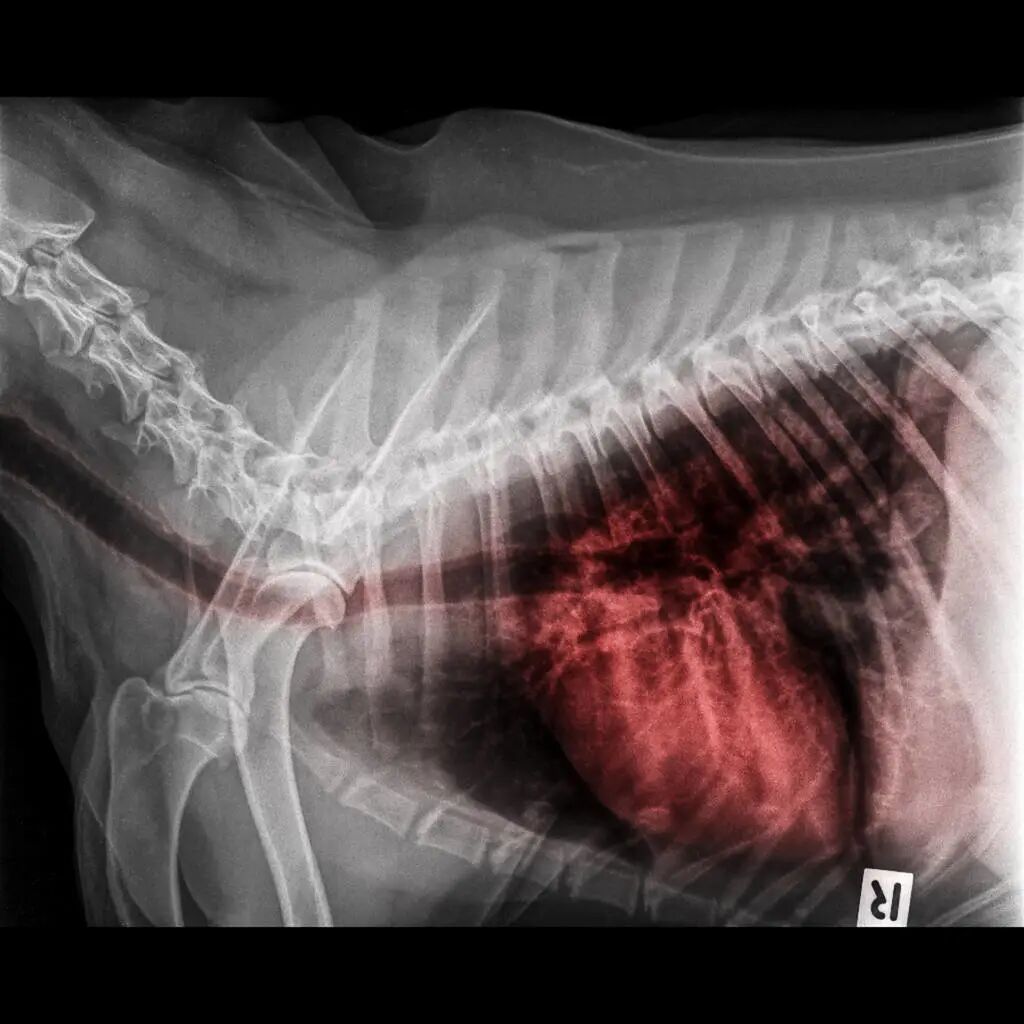

病例2,妊娠期高血压剖宫产术后急性肺水肿。患者,女性,28岁,体重85kg,因第1胎宫内孕38+5周,头痛伴双下肢水肿,不能平卧1个月,不规律宫缩1小时入院。查体:体温36.8°,心率110次/分,呼吸20次/分,血压180/110mmHg,呼吸稍促,心脏彩色多普勒超声:左心室扩大,二尖瓣关闭不全;尿蛋白(++)。血小板90X109/L:肝功能:谷丙转氨酶增高,总蛋白降低;眼底检查示:视网膜水肿,有絮状渗岀。诊断:妊娠期高血压(重度)。

患者术前未行正规治疗。急诊推患者入手术室,开放液路,于右侧卧位下L2-3间隙行腰-硬联合麻醉,见脑脊液流出后缓慢给予0.75%布比卡因2.0ml+10%葡萄糖溶液0.5ml,头向置入硬膜外导管3.0cm,嘱患者仰卧、吸氧、头高脚低位,右髓部垫高20°,调节麻醉平面达T8,手术开始后4分钟取出1男婴,给予咪达唑仑2mg入壶。胎儿娩出后10分钟产妇心率达到130次/分,给予毛花昔C 0.2mg、呋塞米20mg静脉滴注,生命体征逐渐平稳,手术40分钟后结束,出血约300ml,补液500ml,尿量200ml,将产妇安全返回病房。

返回病房20分钟后,患者突然岀现心慌气短,口唇发紺,咳大量粉红色泡沫痰,测血压160/1lOmmHg,心率130次/分,呼吸30次/分,双肺底可闻及细小湿啰音,立即行半坐位,面罩吸氧,毛花昔C 0.4mg,呋塞米20mg,地塞米松20mg静脉注射,5分钟后患者烦躁、呼吸困难加重、出现意识不清,SpO2 70%,急行气管插管接呼吸机行正压通气,吗啡5mg入壶,酚妥拉明20mg+5%葡萄糖溶液250ml缓慢静脉滴注,根据血压变化适当调节滴速,5%碳酸氢钠200ml静脉滴注,氨茶碱0.25g+10%葡萄糖溶液20ml稀释后缓慢静脉注射,呋塞米20mg静脉注射。40分钟后患者意识逐渐清晰,只有很少量的粉红色泡沫痰,测量血压120/75mmHg,心率110次/分,SpO2 92%,双肺底可闻及少许湿啰音。2小时后患者呛咳明显,无法耐受气管导管,吸痰后拔出气管导管。2天后患者排气,开始进流食,可平卧及下地活动,8天后痊愈出院。半月后随访无异常。

重度妊娠期高血压疾病可岀现脑血管痉挛、脑水肿、头痛,个别患者可出现昏迷,甚至发生脑疝;肾小球扩张,血浆蛋白自肾小球漏出形成蛋白尿,血浆肌酔增高,严重时出现少尿及肾衰竭;全身小动脉痉挛,血管通透性增加,血液浓缩、血细胞比容上升、血小板减少,甚至出现微血管病性溶血;肝功能受损,各种转氨酶升高;肝动脉周围阻力增加,严重时门静脉周围坏死;血管痉挛,血压升高,外周阻力增加,心肌收缩力和射血阻力增加,心排血量明显减少,心脏处于低排高阻状态,心室功能处于高动力状态,由于内皮细胞活化使血管通透性增加,导致心肌缺血、坏死,严重时导致心力衰竭和急性肺水肿。

本例属重度妊娠高血压症患者,术前未进行正规的治疗,使产妇的心、肺、肾等功能受到了严重的损害,因术前我们进行了充分的术前准备,术中釆取充分镇静、控制输液量、头高脚低位,术中及时发现心力衰竭的早期症状,釆取了正确的治疗,在一定程度上缓解了病情的发展,但在到达病房后,因患者病情稳定,让产妇采取了平卧位,导致回心血量急剧增加,出现急性左侧心力衰竭、肺水肿等症状。本病例提醒,对重度妊娠高血压症患者术前、术中、术后要及时控制血压,减轻心脏前、后负荷,保持患者生命体征平稳,对可能出现的并发症提前预防。